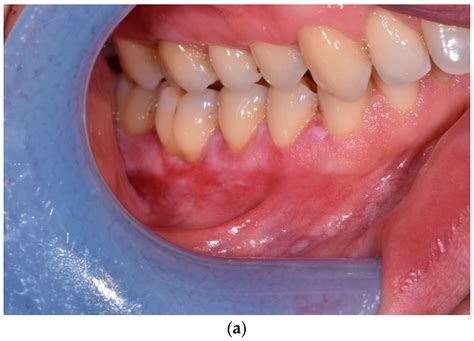

The primary symptom that sets this condition apart is the intense pain associated with the erosions. Patients often describe a burning sensation that intensifies when they consume acidic, spicy, or hot foods. The appearance can be quite alarming, often presenting as:

• Bright red patches: Areas where the outer layer of the mucosal lining has been shed.

• Ulcerations: Open, raw sores that bleed easily.

• White striae: Lacy, web-like white lines surrounding the red or ulcerated areas.

• Gingival involvement: Often manifesting as desquamative gingivitis, where the gum tissue appears raw and peels away.